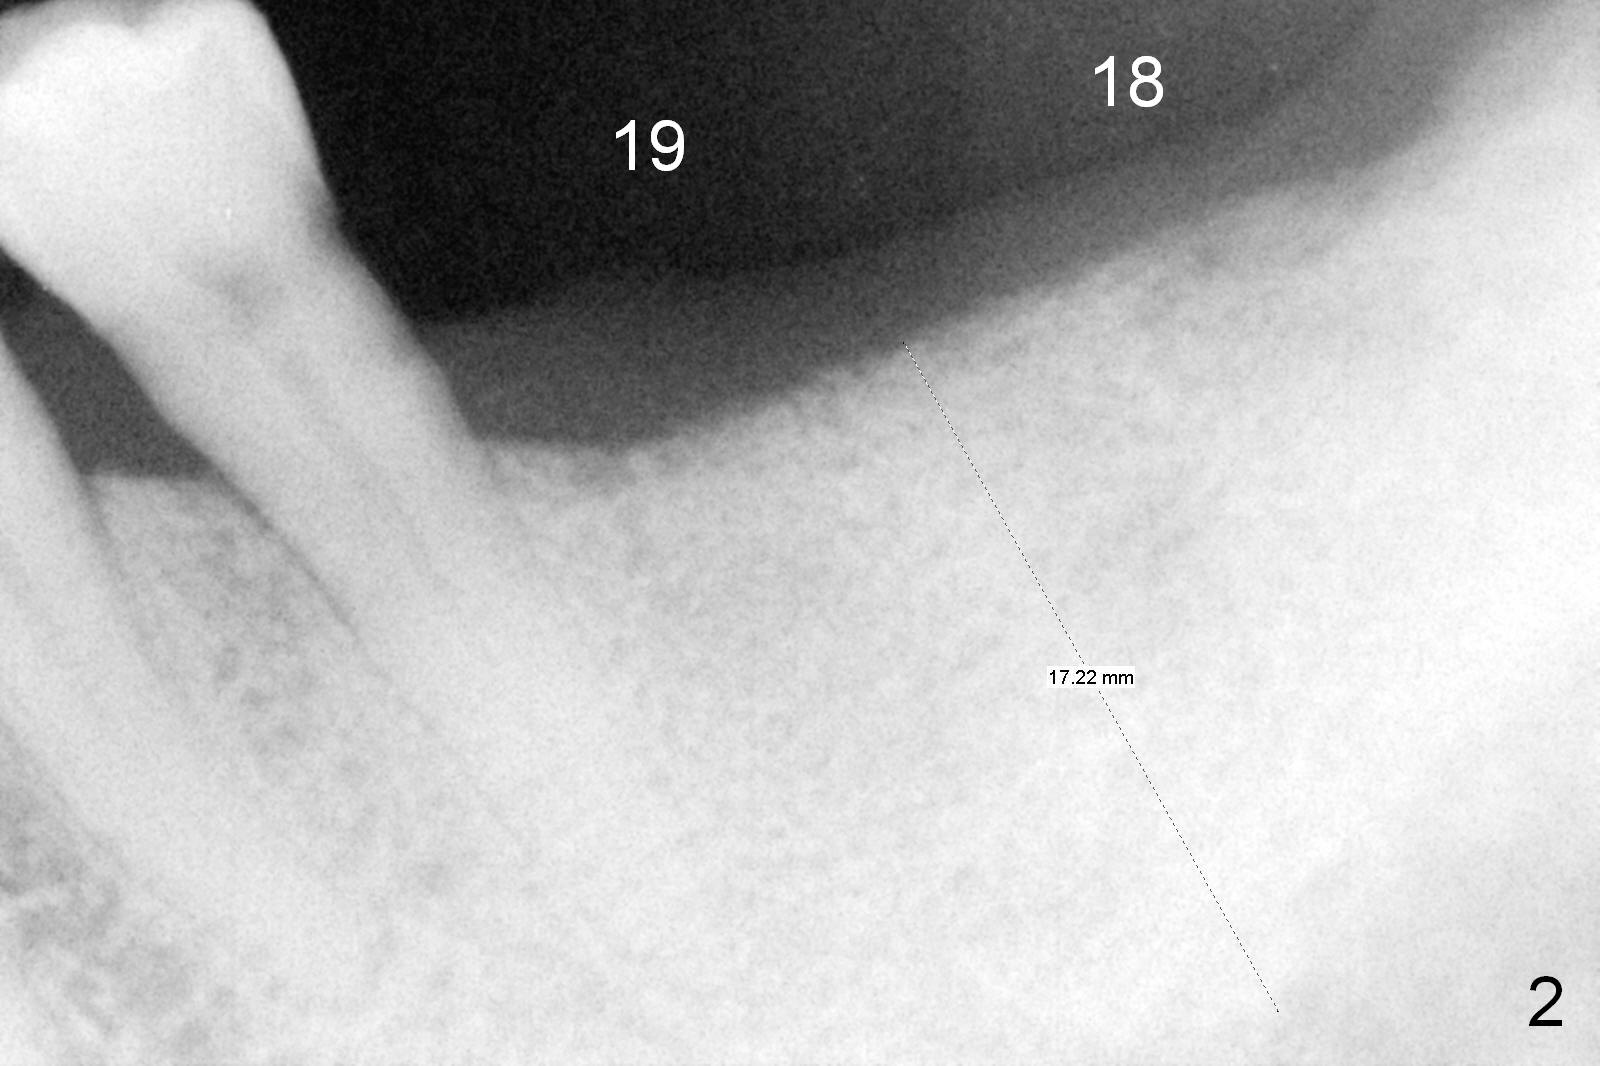

A 64-year-old man has lost 4 molars (Fig.1 posterior view of mounted casts) and is eager to have them back. Implants will be placed at #18 and 19 first (Fig.2). Use surgical stent and starter drill to initiate osteotomies through the gingiva. An incision will be made next. Adjust buccolingual position of the osteotomies. Depth will be 10 and 12 mm at #18 and 19, respectively. Take postop panoramic X-ray for #30 and 31 implant design.

In fact, initial depth for #18 and 19 is 12 mm, quite close to the Inferior Alveolar Canal at #18 (Fig.3 (red dashed line: the superior border of the former). By mistake, the implant at #18 is placed a little deeper than necessary, since the buccal bone is inferior to the lingual one (Fig.4; 5.3x12 mm vs. 5.0x12 mm for #19). As planned, panoramic X-ray is taken immediately postop. Bone height at the 2nd molar decreases drastically as compared to that of the 1st molar, especially on the right side (Fig.5 (abutments: 6.8x5(2) mm for #19, 7.8x5(3) for #18, respectively)). For #30,31 implant placement, initial depth will be 10 and 8 mm, respectively. Follow it faithfully. The implant at #31 could be as large as 5.9 or 6.4 mm to compensate for the length.